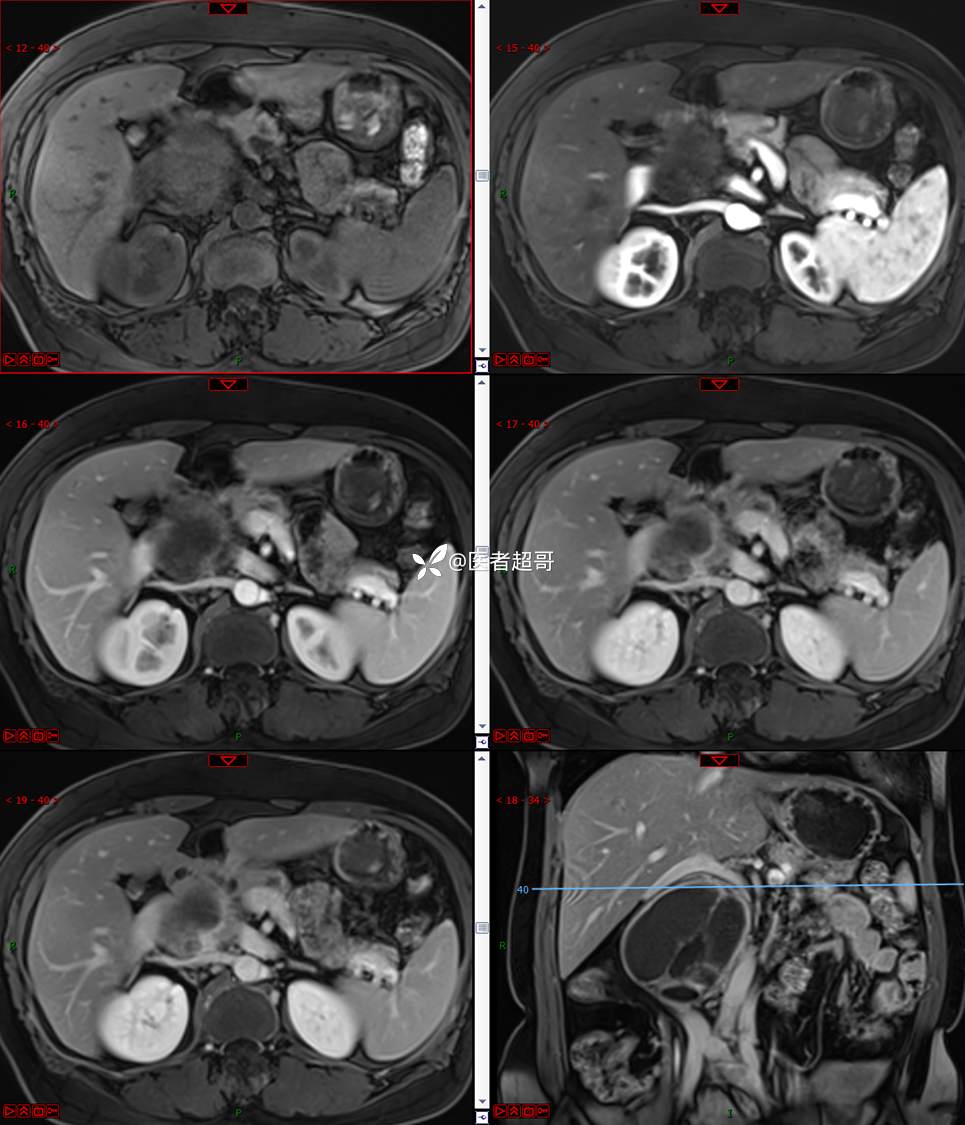

【影诊笔记671】定位有难度,究竟是腹腔内or腹膜后,请先定位,再定性!有结果~~~

专科检查:腹部平坦,腹肌软,无压痛及反跳痛,无包块,肝脾无肿大,Murphy征阴性,腹部叩鼓,肝脾双肾无叩痛,移动性浊音阴性,肠鸣音正常。我院 肝胆胰脾肾彩超提示:脂肪肝、腹腔内囊实性团块,建议进一步检查。